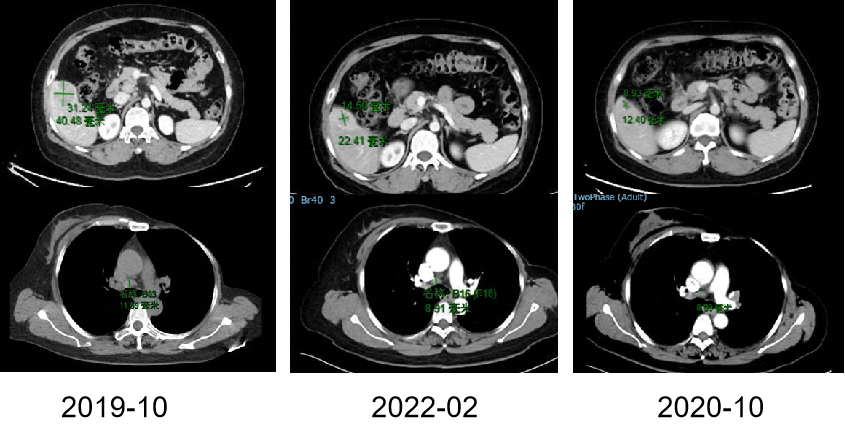

图1